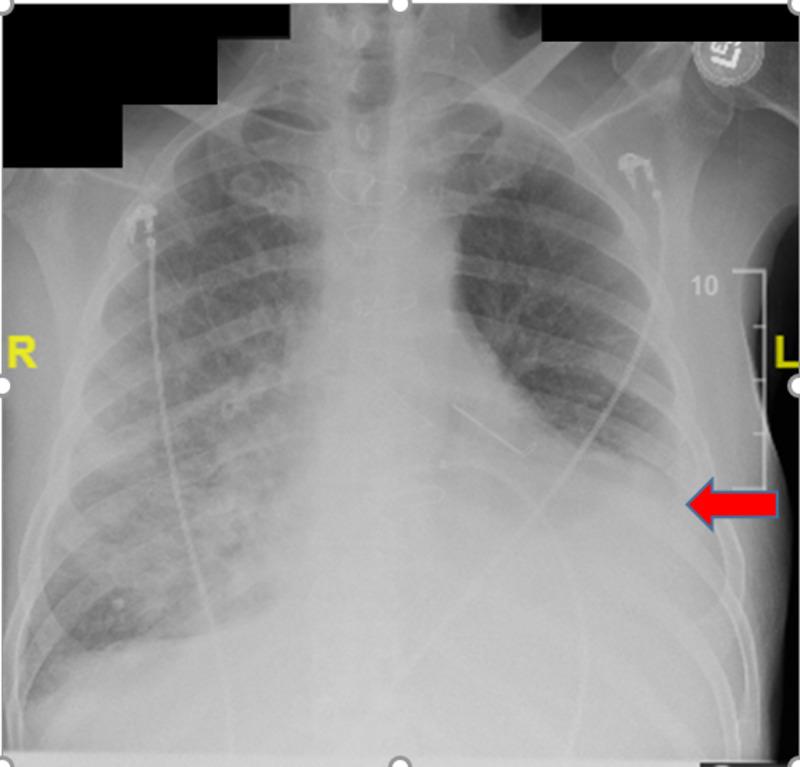

二尖瓣置换术后瓣周漏的复杂病例

A Complicated Case of a Paravalvular Leak Following Mitral Valve Replacement.

Paravalvular leaks (PVL) are an uncommon sequelae of valve replacement but can be seen as a complication of both mechanic and prosthetic valves. Patients with PVL may remain asymptomatic or have detrimental complications, which include heart failure, hemodynamically significant hemolysis, and endocarditis. Management depends on the clinical presentation and the degree of the valvular leak. We hereby present a case report of a patient with a complicated clinical course secondary to a PVL of the mitral valve. The patient had a recent mitral valve replacement and presented with symptoms of heart failure that was refractory to standard medical therapy. Valvular abnormality was not seen with initial trans-thoracic echocardiogram (TTE), but with high clinical suspicion, a trans-esophageal echocardiogram (TEE) was done confirming a PVL. The patient's condition continued to deteriorate; he became hemodynamically unstable with end-organ damage. Cardiothoracic surgery was consulted for surgical repair of the PVL. The patient, however, remained too unstable for surgery and the family opted for comfort measures per the patient's wishes.

摘要

瓣周漏(PVL)是瓣膜置换术后不常见的后遗症,但可视为机械瓣膜和人工瓣膜的并发症。瓣周漏患者可能无症状或出现有害并发症,包括心力衰竭、具有血流动力学意义的溶血和心内膜炎。治疗取决于临床表现和瓣膜漏的程度。我们在此报告一例二尖瓣瓣周漏继发复杂临床过程的病例。该患者近期进行了二尖瓣置换术,出现了标准药物治疗无效的心力衰竭症状。最初的经胸超声心动图(TTE)未发现瓣膜异常,但由于临床高度怀疑,进行了经食管超声心动图(TEE)检查,证实存在瓣周漏。患者病情持续恶化;他出现血流动力学不稳定并伴有终末器官损害。咨询心胸外科进行瓣周漏的手术修复。然而,患者仍因过于不稳定而无法进行手术,家属根据患者意愿选择了姑息治疗措施。